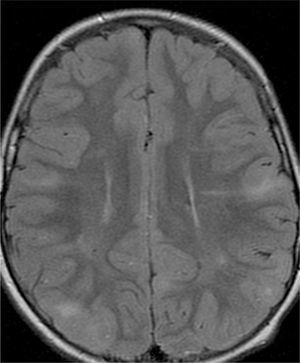

Las resonancias magnéticas (RM) cerebrales evaluadas han sido revisadas de forma independiente por el mismo examinador de la especialidad de Neurorradiología y se estudiaron las siguientes variables: número de tuberomas, localización supra o infratentorial, el número de lóbulos cerebrales con lesiones, el número y la lateralización de tuberomas con quistes, las líneas de migración radial de la sustancia blanca, los nódulos subependimarios y los astrocitomas de células gigantes. Los pacientes efectuaron los estudios de RM en equipos GE Signa 1.5T y en RM Philips Achieva 3.0T TX (3 pacientes), en el Departamento de Neurorradiología del CHP. Después de obtenida la imagen localizadora en el plano sagital, para identificar las comisuras anterior y posterior, se han adquirido imágenes en paralelo al plano intercomisural: FLAIR, T2 SE, T2 *, T1 SE y T1 SE tras contraste.

Para la identificación de tuberomas y líneas de migración radial han sido utilizadas imágenes FLAIR18 y para la identificación de los nódulos subependimarios, imágenes FLAIR y ponderadas en T2.

Se definió tuberoma como una lesión hiperintensa corticosubcortical en FLAIR y líneas de migración radiales como hiperintensidades lineales en FLAIR, que se extiende desde la superficie ventricular hasta el tuberoma cortical. Los nódulos subependimarios han sido investigados en cualquier ventrículo, con origen en la pared ventricular y con proyección hacia el interior de los mismos.

Se consideraron tuberomas con quistes subcorticales las lesiones con una señal similar al del líquido cefalorraquídeo en todas las ponderaciones y con un anillo hiperintenso alrededor en T2. Los tuberomas o nódulos subependimarios calcificados han presentado una hiposeñal en T2 y T2*. Una vez que la cantidad o el número de tuberomas en el parénquima encefálico son indicados como el mejor marcador de gravedad de epilepsia y de la función cognitiva1, se efectuó una evaluación cualitativa por medio la frecuencia de tuberomas. En cada lóbulo cerebral, la densidad de tuberomas se relaciona con la carga de lesión cerebral obtenida por la evaluación del número total de tuberomas y de la afectación de cada lóbulo por los tuberomas. Se consideró como elevada carga de lesión la afectación de todos los lóbulos por tuberomas, en pacientes con número total de tuberomas más de 15. No han sido evaluados la densidad o el volumen de tuberomas por técnica cuantitativa de segmentación automática de tuberomas por inaccesibilidad a software apropiado.

El 74,3% (26) de las RM disponibles han sido revisadas en todos los lóbulos cerebrales en el 76,9% (20) de los pacientes, en los cuales se identificaron más de 15 tuberomas, es decir, una elevada carga de lesión. En el 96,2% (25) de los enfermos se observaron líneas de migración radial (fig. 1). Estaban presentes nódulos subependimarios en el 84,6% (22), la mayoría de los cuales con calcificación y, en 3 casos, con captación de contraste (fig. 2). En el 23,1% (6) de los enfermos se encontraron tuberomas infratentoriales. Siete casos presentaban tuberomas con aspecto quístico (26,9%), 6 de los cuales en localización yuxtacortical y uno infratentorial (fig. 3). Es de referir un caso con probable astrocitoma de células gigantes, bajo control dimensional, en la región del agujero de Monro, sin signos de hidrocefalia (fig. 4). Ninguno de los enfermos presentaba atrofia focal.